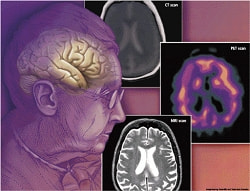

心の病気の中には、うつ病とよく似ている病気があります。医師は診断にあたっては、うつ病なのか他の心の病気なのか、慎重に判断することになります。うつ病と症状が似た病気である認知症(アルツハイマー型)について紹介します。

「アルツハイマー型認知症」と「脳血管性認知症」がある

どちらも初期の症状は記憶障害が中心なり、進行に応じて精神機能や知的機能が低下していきます。